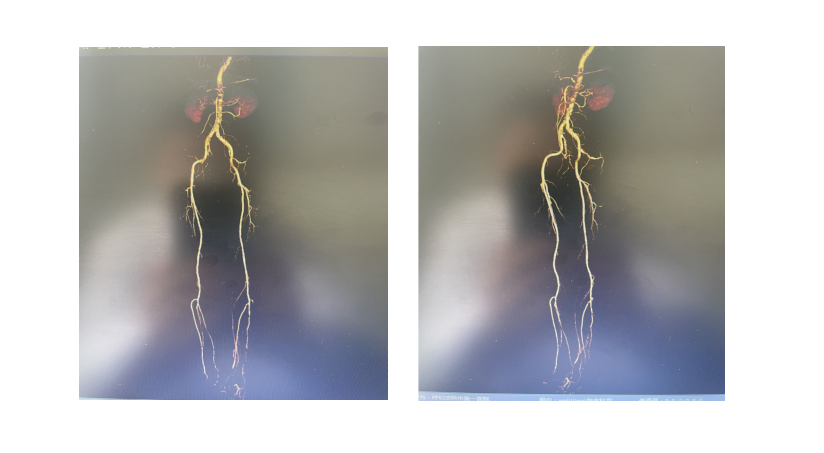

下肢动脉CT三维成像示:左侧股动脉下段并腘动脉节段性管腔狭窄开始胫骨横向骨搬移,创面清创不扩创,保持引流通畅。